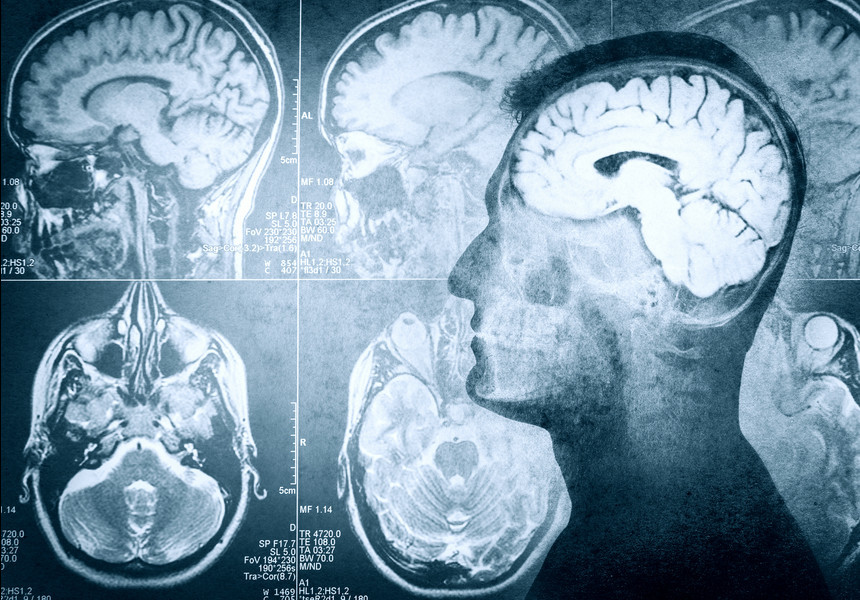

Voluntarii, în rândul cărora s-a aflat şi Alex Huth, coordonatorul studiului, au ascultat mai mult de două ore de poveşti difuzate în programele unor posturi radiofonice americane, în timp ce se aflau în interiorul unui dispozitiv de imagistică prin rezonanţă magnetică.

Cercetătorii americani au colectat astfel o serie de date medicale, precum modificările fluxului sangvin şi ale nivelului de oxigenare – indicatori ai activităţii cerebrale – în diferite zone din cortextul cerebral.